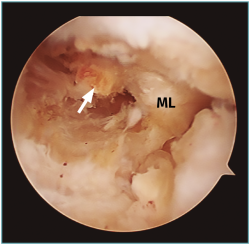

Se han descrito varios signos radiológicos relacionados con las roturas de la raíz y las roturas radiales en general, como son el signo del triángulo truncado, el signo de la hendidura en el plano coronal y el clásico signo del menisco fantasma en el plano sagital(57). El signo del menisco fantasma o del menisco vacío se observa en el contexto de una extensa rotura radial que atraviesa el espesor completo meniscal, o posterior a meniscectomía, cuando el plano de corte se realiza en el plano exacto de la rotura(58)(Figura 6).

Figura 6. Imagen sagital de resonancia magnética en la que puede apreciarse el signo del “menisco fantasma” (flecha).